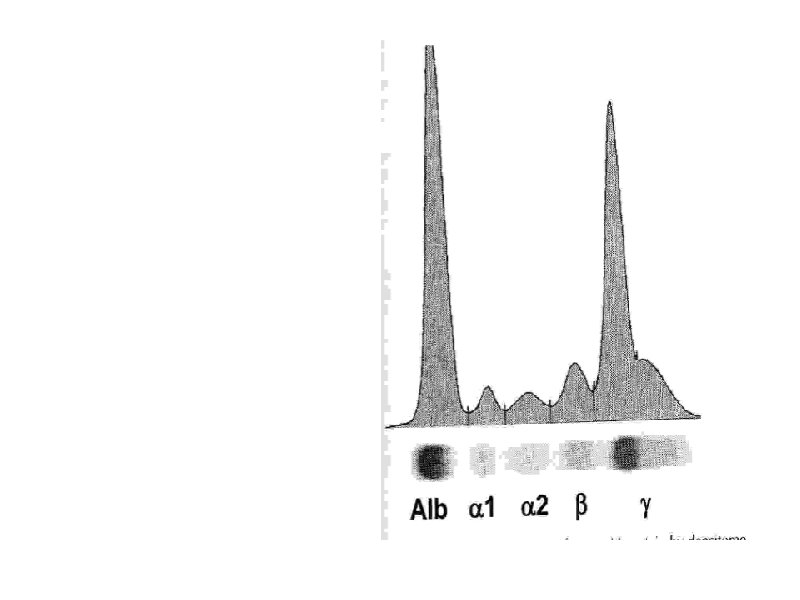

Лечение макроглобулинемии Вальденстрема